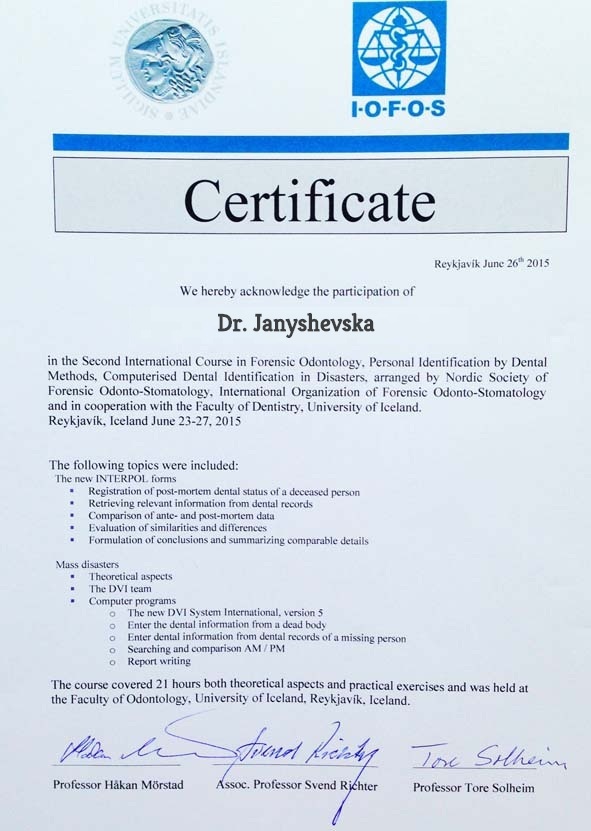

Сертифікати

Наша клініка повністю ліцензована